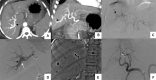

Hepatic arterioportal fistula (APF) in the setting of cirrhosis may aggravate the preexisting portal hypertension and its complications. Cirrhotic patients undergo various percutaneous invasive procedures and are at risk of developing an APF. These should be diagnosed early and should be treated accordingly at the earliest when indicated. Presently embolization is the treatment of choice with coil embolization as the most commonly used method. We describe four cases from our institute with a history of liver parenchymal disease and were found to have acquired APF on imaging. These were successfully managed with transarterial embolization with resolution or improvement in their clinical symptoms on follow-up. The present case series and review emphasize the importance of APF in the setting of liver parenchymal disease and the role of early diagnosis and therapeutic intravascular interventions.